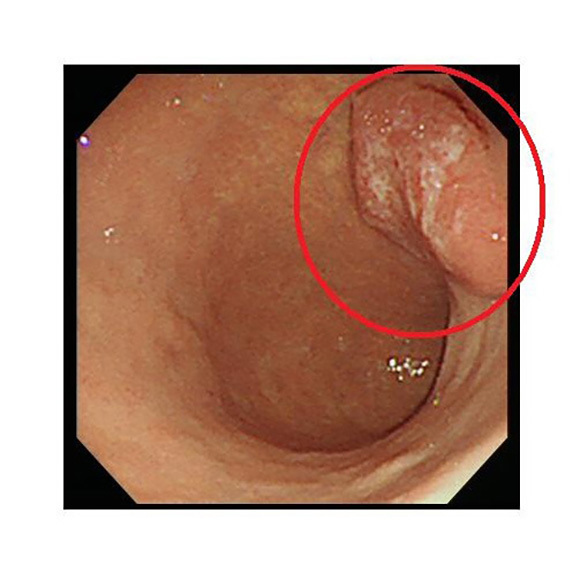

NBI:狭帯域光法システムで光を照らして観察します

NBI

食道・胃・大腸内の様子を明確に画像表示し、より癌を見つけやすくなりました。